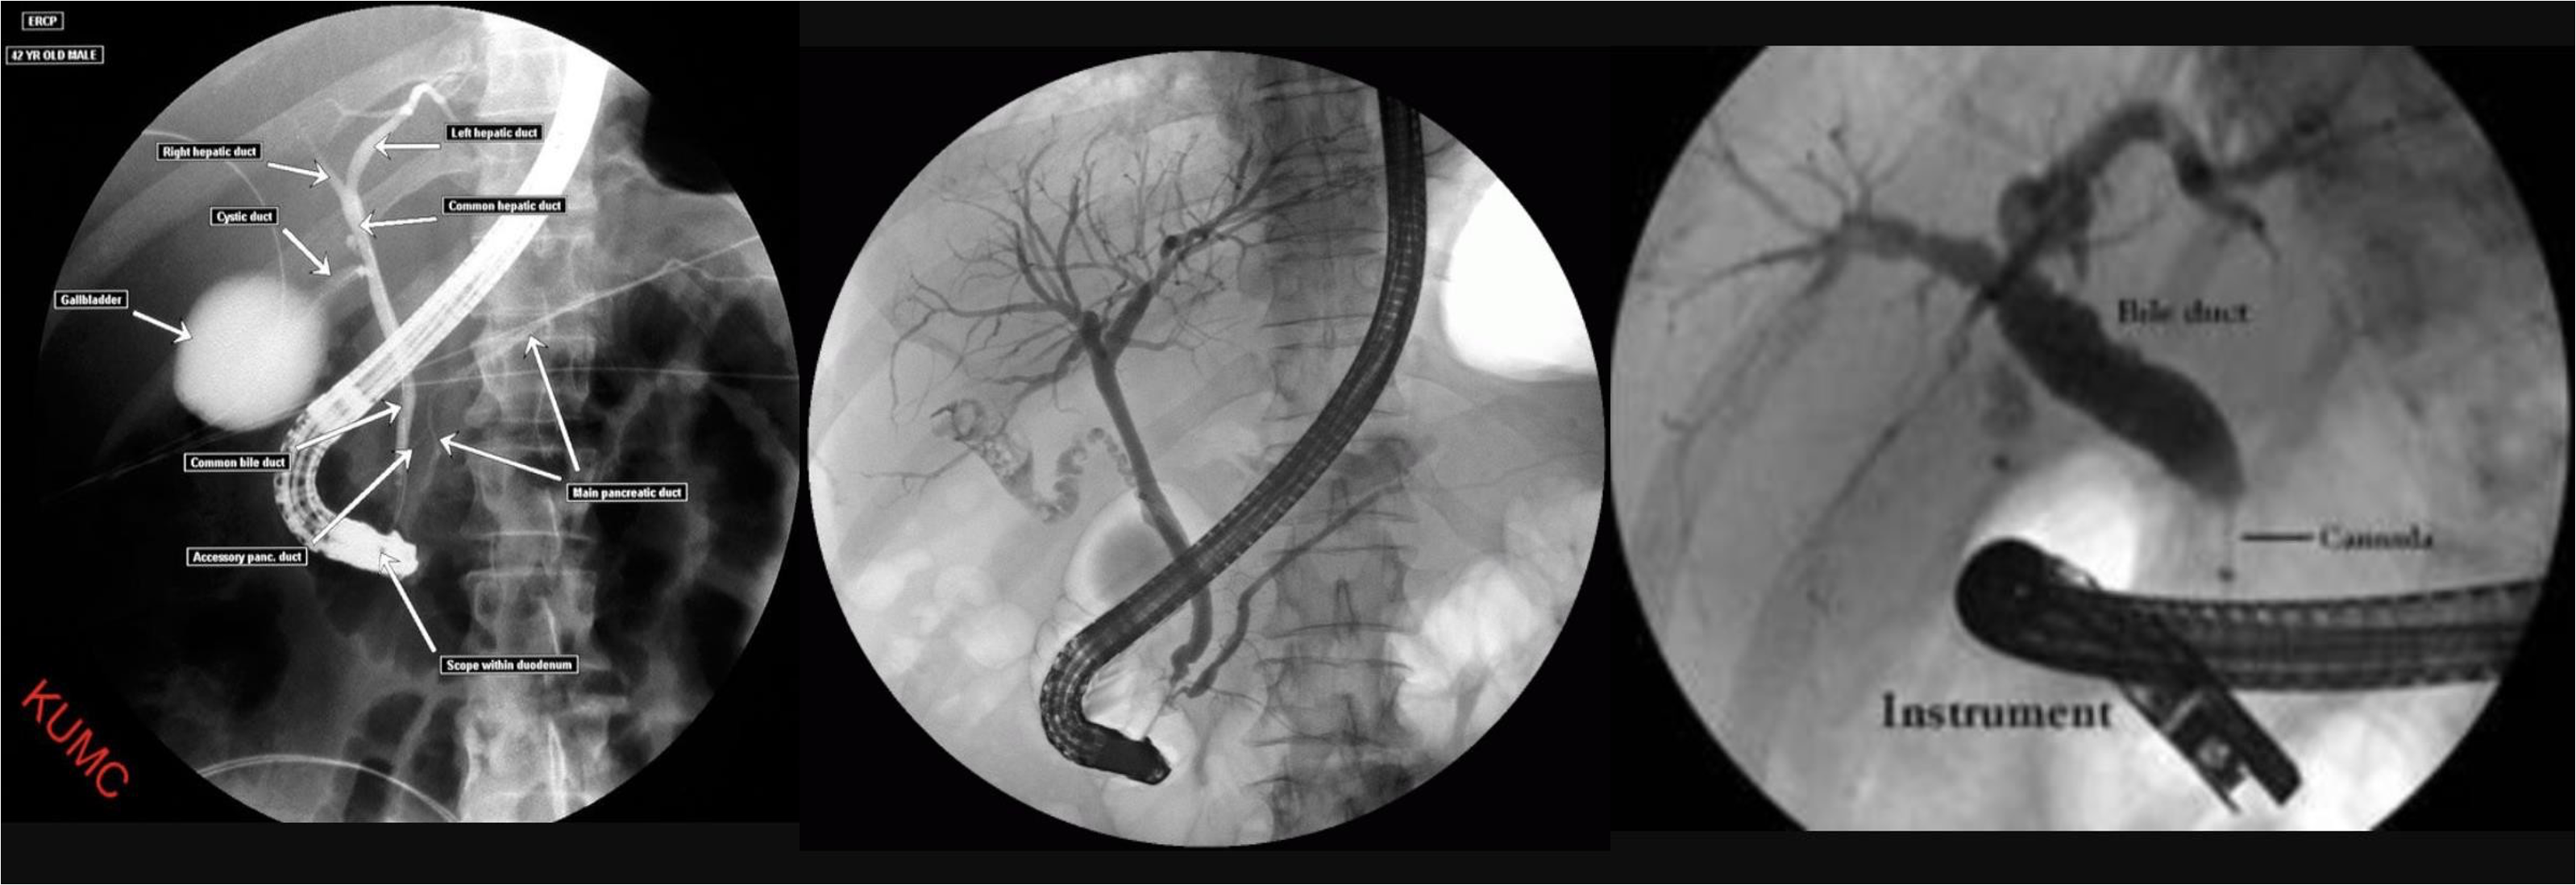

ERCP

- ERCP

- ERCP dilated (diff stone, tumour)

- dilated cbd, stone

- 3 - d. basket?

MRCP

diagnostic therapeutic anatomical